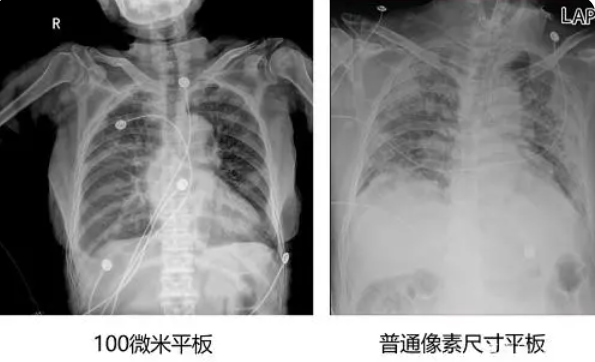

同時移動DR也因其輻射劑量小,可采用遠程遙控曝光,減少了醫(yī)務(wù)人員和患者的輻射承受,操作簡單、移動方便的特性,可直接到病房床邊做檢查。特別在疫情時候,尤其適用于重癥及危重癥新冠患者。重癥及危重癥新冠患者病情危重,往往不易離開病房去科室檢查,而移動DR可直接到病房床旁拍片,立即得到影像資料,及時評估患者病情,為治療方案的調(diào)整和患者的成功救治爭取時間,此時移動DR檢查無疑是觀察肺部病灶的最佳手段,移動DR拍攝的圖像質(zhì)量好壞也顯得尤為重要,得益于百微米高清平板探測器技術(shù)的發(fā)展,也讓移動DR步入了更高清的成像時代,通過百微米大板移動DR拍攝的床旁胸片能生成更清晰的胸部影像,并且1800萬超高像素有效展示了更多的胸部影像細節(jié);通過對比100微米大平板影像與普通像素尺寸平板的影像,可以看到百微影像對比度適中,圖像清晰度更高,成像細節(jié)更加豐富;在胸部影像顯示中肺門影結(jié)構(gòu)、肺紋理等細節(jié)展示更清楚,兩側(cè)膈肌邊緣、心臟、縱隔邊緣清晰銳利顯示,在影像中都可以清晰地顯示胸部細微結(jié)構(gòu),滿足臨床診斷要求。也使得移動DR更貼近臨床。